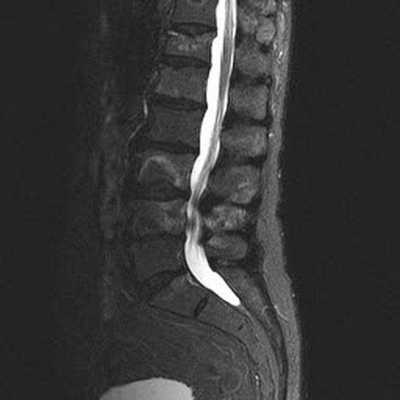

МРТ позвоночника. Т2-взвешенная МРТ, срез через межпозвоночное отверстие. Красные стрелки - корешки. Межпозвоночное отверстие обведено малиновым. P- ножка дуги. VB - тело позвонка.

МРТ позвоночника. Аксиальная Т2-взвешенная МРТ. Нормальный срез через дугоотростчатые суставы.